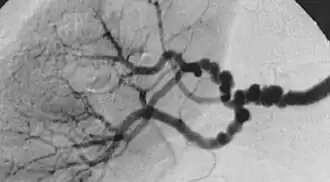

Aspect « en collier de perles » ou « en pile d'assiettes » à l'angiographie d'une dysplasie fibromusculaire de l'artère rénale.

La dysplasie fibromusculaire (DFM) est une maladie systémique de l’artère, non athéroscléreuse et non inflammatoire. Elle touche les artères de moyen calibre, en particulier l'artère rénale et l'artère carotide interne. La dysplasie fibromusculaire se caractérise par un épaississement anormal de la paroi artérielle, provoquant des rétrécissements et des dilatations localisés. Ces altérations vasculaires présentent un aspect typique semblable à un « collier de perles » à l'examen d'imagerie médicale.

Les formes de dysplasie fibromusculaire sont classées selon l'apparence des artères lors de l’examen d’imagerie médicale d’angiographie selon la recommandation du First International Consensus on the diagnosis and management of fibromuscular dysplasia (2019). L’angiographie permet de distinguer les DFM focales (sténose unique et unilatérale) et multifocales (sténoses multifocales, aspect typique de « collier de perles »). La forme multifocale est la plus courante puisqu’elle se rencontre chez 80 à 90% des cas[6].

Historiquement, la classification de la DFM était basée sur l’histologie, en fonction de la couche (ou tunique) de la paroi artérielle touchée. Dans la plupart des cas, les atteintes se situent au niveau de la media, la couche moyenne de l’artère. L’alternance d’accumulation de collagène et de perte de membrane élastique dans cette tunique produit l’aspect « collier de perles » visible à l’angiographie. Dans de plus rares cas, l'intima ou l'adventice peuvent être touchés. À l’angiographie, ces formes apparaissent comme des rétrécissements isolés.